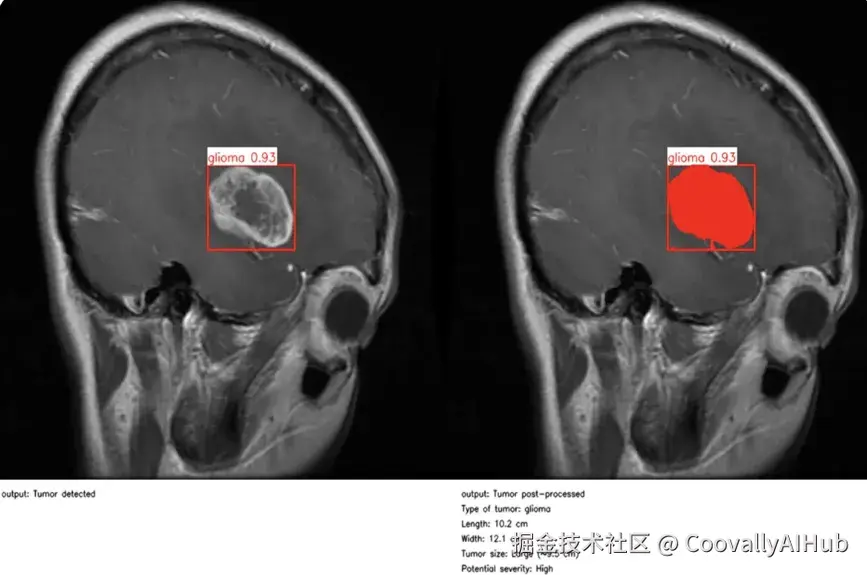

同样,随着计算机视觉成为日常临床工作流程的一部分,医疗保健领域也取得了重大进展。在医疗环境中,精确性和时间性至关重要,而计算机视觉研究和人工智能驱动的图像分析正在让临床医生做出更快、更明智的决定。

医疗保健的许多领域都是如此。以眼科为例。在英国莫菲尔德眼科医院,研究人员开发了RETFound,这是医学领域首批人工智能基础模型之一,也是眼科领域的首个人工智能基础模型。

通过自我监督学习,该模型在 160 万张视网膜图像上进行了训练,可以detect 糖尿病视网膜病变和青光眼等威胁视力的疾病,甚至可以根据细微的视网膜线索预测心力衰竭、中风和帕金森病等更广泛的全身性疾病。